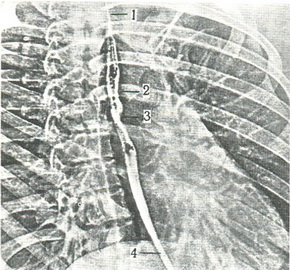

Рентгенограми стравоходу бувають оглядові і прицільні, виконані в бічній, правій і лівій косій проекціях. У цьому випадку стравохід добре видно в задньому середостінні між хребцями і серцем (рис. 229). Густа маса контрастує стравохід інтенсивно, рідка маса, прийнята невеликими порціями, тільки контурирует складки слизової оболонки. У першому випадку буде видно звуження, вигини і ширина контрастного грудки до 1-2 см, у другому випадку - архітектура складок і вигини стравоходу. При зміні рельєфу слизової оболонки або утворення додаткових звужень розширення вигинів відображає ураження не тільки стінки стравоходу, але й поряд лежачих органів: бронхів, трахеї, серця, хребта, кореня легкого або лімфатичних вузлів заднього середостіння. Черевна частина стравоходу розглядається так само, як і інші його відділи. На рентгенограмі в прямій проекції рівень стравохідного отвору в діафрагмі збігається з місцем його вигину. Між тінню стравоходу і повітряним міхуром склепіння шлунку в нормі є кут. Більш достовірна рентгенологічна картина виходить при рентгенокинематограмме глотки і стравоходу. Цим методом послідовно проводиться рентгеносъемка зі швидкістю 6-12 кадрів в секунду, що дозволяє простежити всі фази проходження барієвої маси. У перший період, коли проходить масивний грудку барієвої маси, оцінюються контури стравоходу, а в період проходження повітря і осіли частинок контрастної маси вдається виявити складки і рельєф слизової оболонки.

229. Электрорентгенограмма грудної клітки в першій косій проекції. Стравохід контрастирован (за Н. Р. Палееву). 1 - шийне звуження; 2 - звуження на рівні дуги аорти; 3 - звуження на рівні бронха; 4 - нижнє звуження.  |